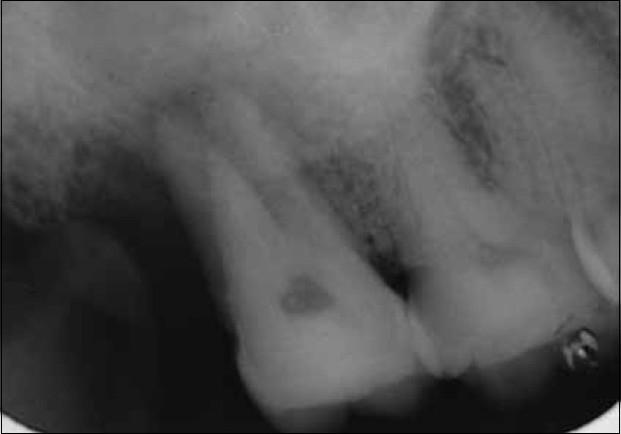

Maxillary right second molar with two palatal root canals.

We report a clinical case of maxillary right second molar with two palatal root canals. The morphology is atypical because it is characterized by two palatal roots with two canals with widely separated orifices and canals. Modifications to the normal access opening and examination of the pulpal floor for additional canals are stressed.